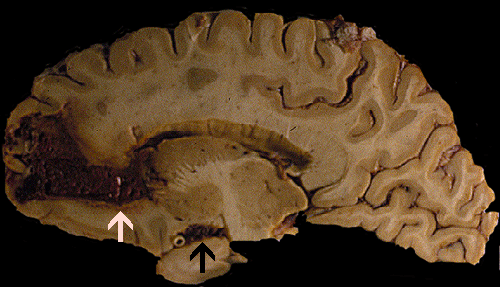

Gross: On external examination of the body, there was no bruising, hemorrhage, or other signs of trauma. The brain weighed 1,300 grams. The cerebellum and brainstem were within normal limits. A large hemorrhage was present in the right frontal lobe (Panel A). The hemorrhage is rimmed by a thin layer of golden brown tissue indicative of hemosiderin deposition that would be produced by old, resolved hemorrhage  (White arrow in Panel A). The hemorrhage also extends into the ventricle, without dilating the ventricles, and into the basal subarachnoid space (Black arrow in Panel A). On the left frontal tip and bilateral temporal tips, there were some small areas of golden brown discolorations in the leptomeninges that were consistent with resolved small subarachnoid hemorrhages.

Comment on gross pathology: The golden brown discoloration in the leptomeninges of the temporal tips is probably due to small hemorrhage because of minor falls as the patient has been alcoholic. The question is whether the large hemorrhage related to his fall. The hemorrhage can be produced by trauma but the extent of hemorrhage, however, seems to be out of proportion to a minor trauma as described by the family members of the deceased patients. Since the fall has occurred 2-3 weeks before, the hemosiderin deposition may be resulted from the hemorrhage triggered by that fall. It can also be resulted from prior hemorrhages. The center of the hemorrhage had some spongiotic changes that could suggest a ruptured hemangioma. Other etiologies including coagulopathies, cocaine abuse, vascular malformations and hemangiomas, and vasculopathies were also entertained. The lack of hemorrhagic lesions in other parts of the brain and the body does not support a diagnosis of coagulopathy.